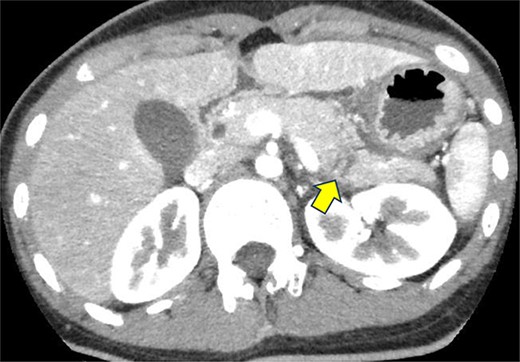

On the fifth day, the ascitic fluid increased in volume, and an open distal pancreatectomy was considered. However, her condition was stable. CT-guided abdominal drainage was performed, and a 10 Fr drainage tube was inserted for peritoneal lavage (Fig. 4). EUS-guided transgastric drainage of the pseudocyst in the omental bursa was performed. The pseudocyst was punctured; a balloon was dilated through the posterior wall of the stomach (Fig. 5a–c), and three tube stents of 7 Fr were implanted (Fig. 5d). The Amy and P-Amy levels in ascites were 9429 and 8877 IU/L, respectively; then, peritoneal lavage was performed daily. On the 12th day, contrast-enhanced CT revealed reduced pseudocyst size (Fig. 6). The patient was discharged on the 16th day (Fig. 7). Three years later, the patient is living her daily life without any complications.

CT of the pelvic region on the fourth day. An increase in ascitic fluid was observed. CT-guided abdominal drainage was performed, and a 10 Fr drainage tube was placed.